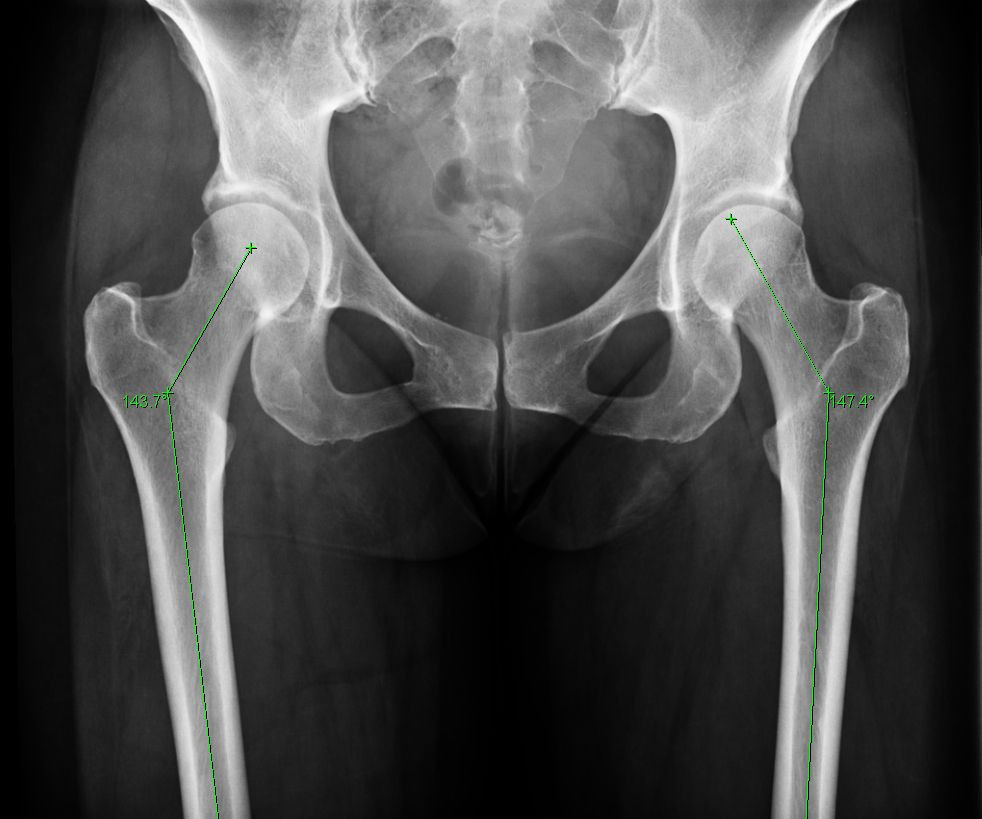

Năm 1895, nhà vật lý Đức Wilhelm Rontgen phát minh ra tia X, giúp khám phá cấu trúc xương bên trong cơ thể mà không cần phải mổ banh xác ra như trước.